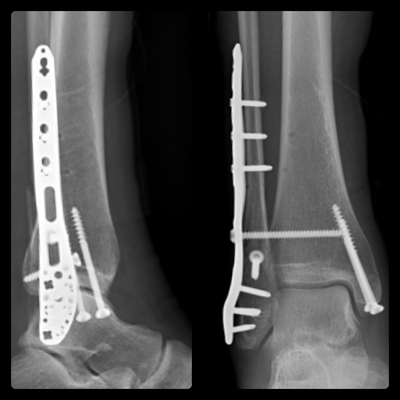

Интересно, у меня тоже левая нога, 2 пластины на МБК и ББК, ходил недели 3 на iwalk, потом на двух подмышечных костылях, потом на одном, сейчас трость, пытаюсь ходить без неё, тоже могу начать прогулку без трости, потом в конце приходится помогать.

У меня ДТП. Я за рулём, на меня на встречку вылетел лоб в лоб. Очнулся в больнице. Левую ногу и левую руку собирали. Вот на руке шрам страшный. Из последствий нога короче на 3см. Спец обувь. А так, спустя 1,5 года всё отлично)))) но металл пока во мне. Не знаю, буду вынимать или нет. И так натерпелся операций, не хочу....